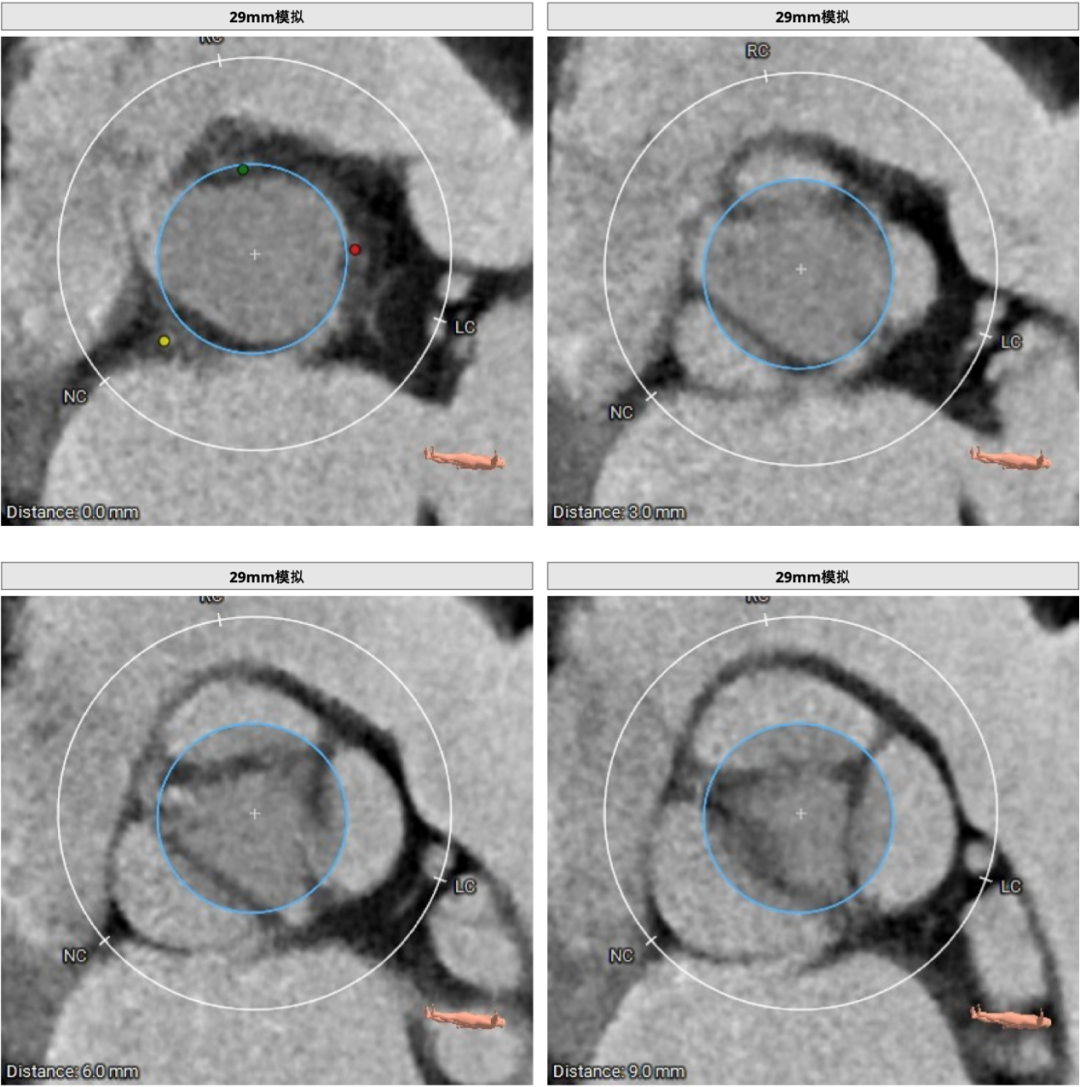

CT分析

患者主动脉瓣三叶式,瓣叶基本等大,窦部增宽,瓣叶增厚,瓣叶游离缘轻度钙化。主动脉瓣环周长折算直径约29.6mm,瓣环周长为92.9mm。

29mm瓣膜植入效果